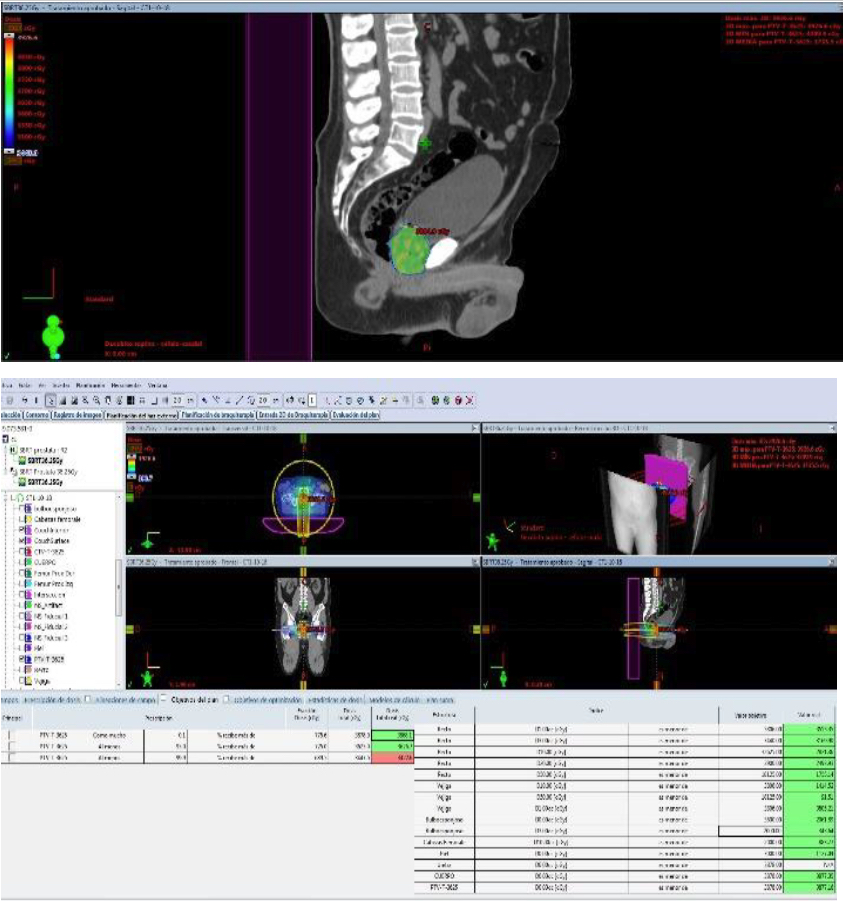

Se presentan figuras de un caso clínico de nuestro centro. Paciente de 57 años, APE: 6.5, Biopsia Gleason 7 (3+4) 2/6 sextantes. Etapificación (-), Rechaza cirugía.